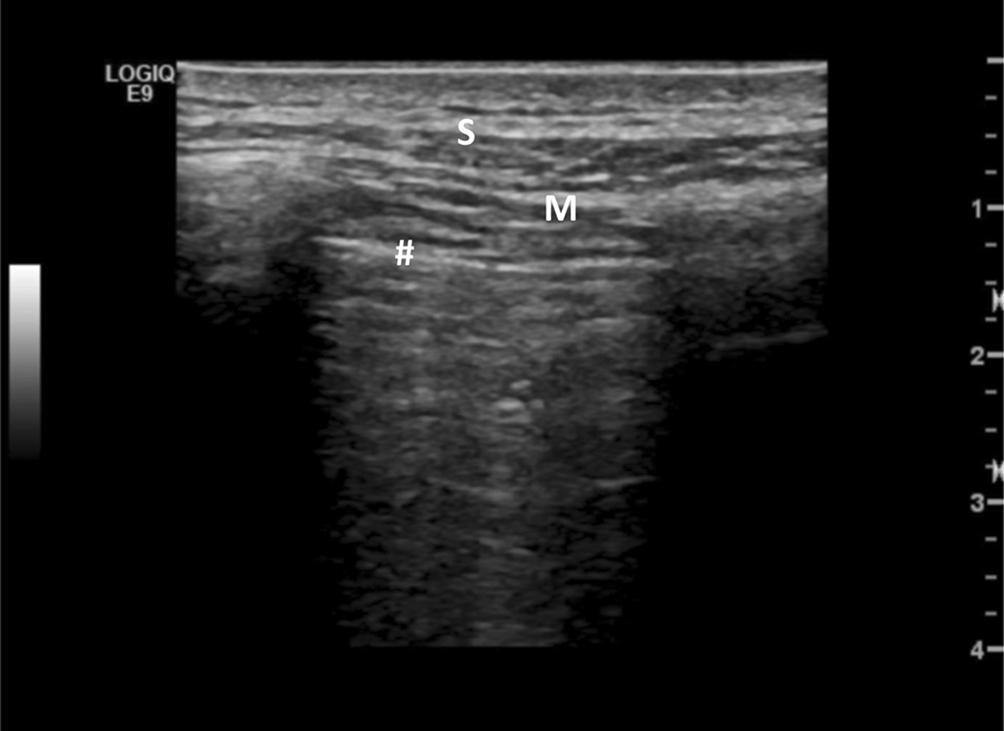

Neben den Kometenschweifartefakten wird auch eine Verbreiterung der Pleuralinie auf ≥ 3 mm in jeglicher Region als pathologisch gewertet [23]. Als Pleuralinie wird die Grenzzone zur belüfteten Lunge beschrieben, bei der es zu einer Totalreflexion der Ultraschallwellen kommt. Obwohl die Pleura selbst aufgrund ihrer geringen Breite nicht durch den Ultraschall dargestellt werden kann, wird die Pleuralinie von vielen Autoren etwas vereinfacht mit der Pleura gleichgesetzt (Abb. 4).

Abb. 4

Lungen-US Normalbefund. S subkutanes Fettgewebe, M Muskulatur, Raute Pleuralinie